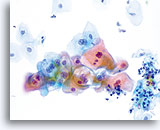

En raison de leur morphologie, les cellules issues de lésions de bas grade comptent parmi les anomalies intra-épithéliales les plus faciles à localiser et à identifier. En comparaison, les noyaux LSIL sont les plus grands et présentent un rapport N/C inférieur aux HSIL ou carcinomes. Ces cellules affichent une atypie nucléaire plus importante que les ASCUS (ce qui se traduit par une augmentation de la taille nucléaire, une irrégularité de la chromatine et une irrégularité de l’enveloppe nucléaire). Les noyaux peuvent occasionnellement ne pas être aussi hyperchromatiques que sur les frottis conventionnels, mais ils le sont toujours par rapport aux cellules normales environnantes. Les changements associés au HPV (par exemple, formation de cavités dans le cytoplasme) sont plus évidents grâce à la fixation liquide et à la technique de transfert, ce qui élimine la déformation des cellules associée à la méthode d’étalement conventionnelle. La méthode ThinPrep préserve mieux ces changements cellulaires, ce qui permet une meilleure distinction entre les véritables cavités cytoplasmiques induites par le HPV et les vacuoles bénignes/dégénératives et/ou les cellules malpighiennes glycogénées.

Comme il s’agit de cellules malpighiennes matures, elles gardent leur forme polygonale et conservent en partie leur taille normale. La taille des noyaux est au moins 3 à 4 fois supérieure à celle d’une cellule intermédiaire normale. En revanche, quand les changements associés au HPV sont évidents, les cellules peuvent être plus petites (quasiment parakératosiques), tout comme les noyaux (quelque peu pycnotiques) qui présentent en outre une binucléation et/ou multinucléation. Ces noyaux pycnotiques affichent en outre des caractéristiques anormales : hyperchromasie, augmentation de la taille par rapport à une cellule malpighienne superficielle normale, légère variation de la forme et de la taille, etc. Il est important d’insister sur le fait qu’une interprétation de LSIL/HPV implique des cavités cytoplasmiques nettes accompagnées de la morphologie nucléaire anormale décrite ci-dessus.